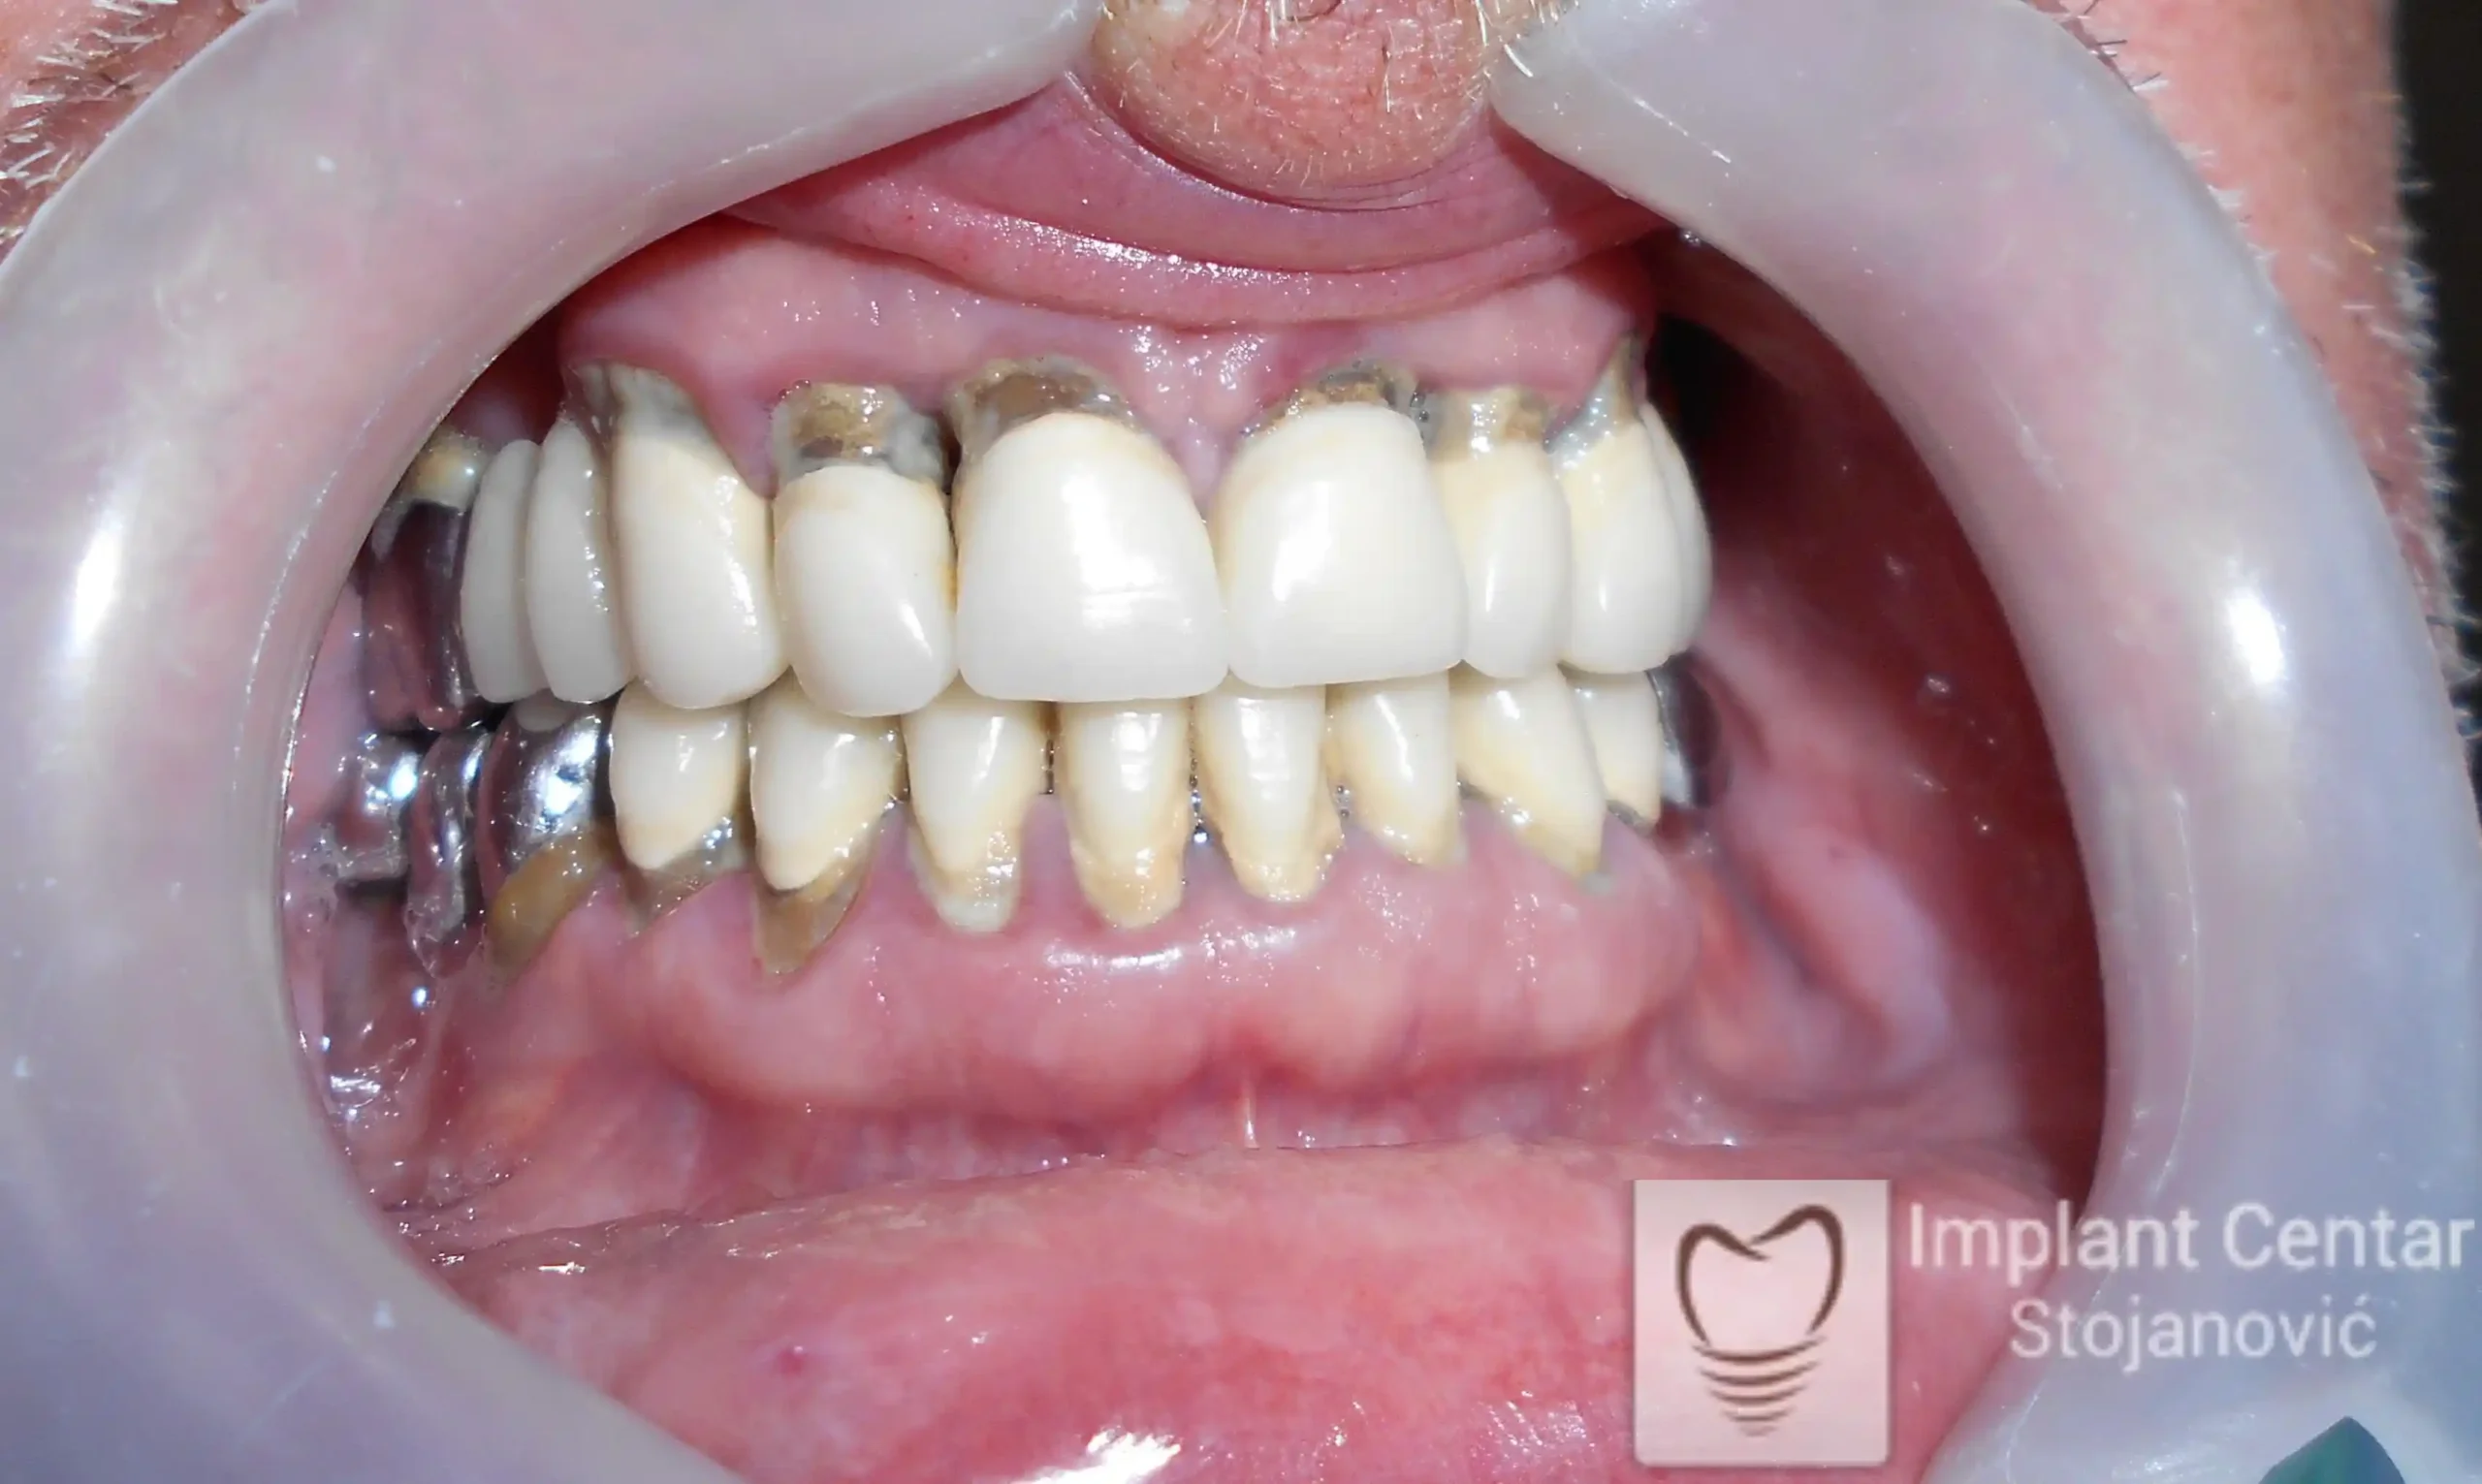

U ovom slučaju prikazujemo potpunu transformaciju osmeha pacijenta koji je imao obrnut zagriz koji smo rešili trajno i funkcionalno pomoću implantata.

Na slici 1. slici 2. vidi se početno stanje — pacijent je imao prirodne zube, ali samo izradom novih mostova nije bilo moguće postići normalan odnos gornjih i donjih zuba (eugnatan zagrižaj).